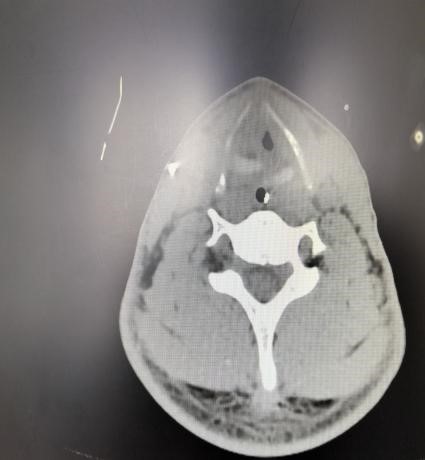

患者入院时虽神志尚清,但已出现声音嘶哑、颈部疼痛、胸闷气喘等危险信号,血氧饱和度持续下降。我院急诊团队评估后立即启动最高级别预警,迅速完成生命体征监护和检查的同时,敏锐地察觉到患者颈部正在快速肿胀,这是皮下气肿的典型表现,预示着气道可能存在严重破损。我院耳鼻喉科专家通过喉镜探查,做出了关键性判断:高度怀疑喉软骨骨折、气管断裂。后续CT检查结果印证了这一判断,患者双侧颌面部、颈部、胸部乃至纵隔内出现了大量积气。更危急的是,断裂处漏出的气体已形成双侧张力性气胸,双肺被压缩均近50%,心脏和大血管严重受压,情况十分危急!

随后,患者被转入EICU(急诊重症监护室)进行高级生命支持。面对创伤性湿肺、纵隔皮下大量气肿、潜在的感染风险以及脑积水等复杂情况,在全身麻醉下,我院耳鼻喉科、麻醉科、呼吸内科等科室组成的专家团队为患者进行了急诊手术。术中发现患者环状软骨下方多个气管环前方碎裂,右侧环状软骨缺损严重。手术团队精准操作迎难而上,为患者精细清创,彻底清理了颈部淤血及游离的碎骨片,为重建创造基础。随后,在纤维内镜辅助下进行气道探查,明确损伤范围,确保无遗漏。同时,术中巧妙地将右侧咽壁内环状软骨膜与左侧带状肌缝合,顺利完成喉部功能重建,并缝合了颈前碎裂的气管。手术最后顺利拔除临时细套管,更换为更安全的7.5号气切套管,保障了术后气道的通畅与安全。